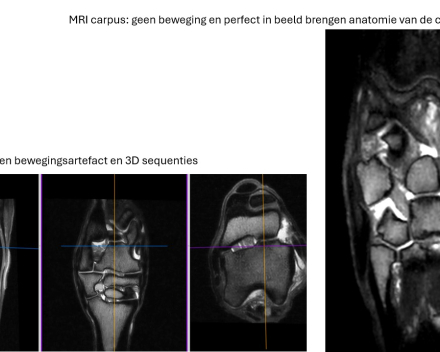

Slide 1 > MRI tarsus: no motion artefact and 3D sequences - MRI carpus: no movement and perfect imaging of the anatomy of the carpal ligaments

Because MRI scans are performed under general anaesthesia, we can guarantee good image quality without motion artefacts. By always striving for the highest possible image quality, we ensure the most accurate diagnosis possible.

Indications for an MRI scan in horses include imaging soft tissue injuries and bone and cartilage injuries to the limbs. Another indication is a brain disorder (neurological disorder). Unlike a standing MRI scan of the limbs, our lying MRI scan produces no or very minimal motion artefacts.